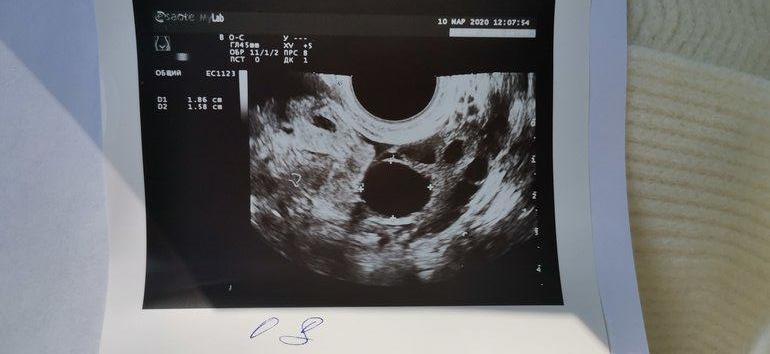

СтимуляцияДевочки! Стимуляция у меня 2-5 ДЦ 100МГ КЛОСТА, сегодня 9ДЦ, почуяла попой что срочно надо сходить на УЗИ И ВОТ ЧТО!

Что делать? ( это первая моя овуляции за все время, первая стимуляция и вот они доминанты!!! Но как быть с эндометрием помогите((